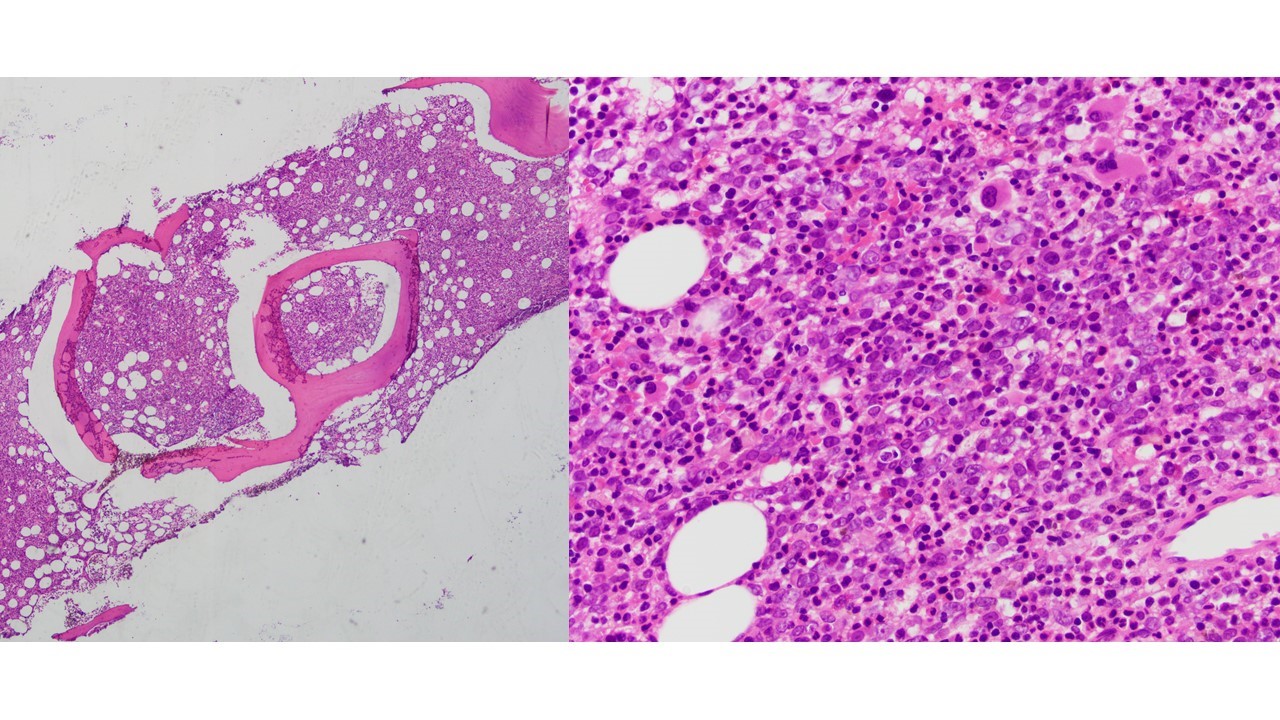

Megakaryoblasts are medium/large cells with dark blue vacuolated agranular cytoplasm. Cytoplasmic projections (blebs and pseudopods) resembling platelets, irregular cytoplasmic borders and cytoplasmic zoning maybe seen. Nuclei are round or slightly indented with finely reticular, dense chromatin and 1-3 nucleoli. Myelofibrosis or increased marrow reticulin is common fibrosis due to megakaryoblast secretion of fibrogenic cytokines, which makes marrow aspiration difficult.

Bone marrow features dysplastic small, mono- and bilobed megakaryocytes with accompanying multilineage dysplasia.